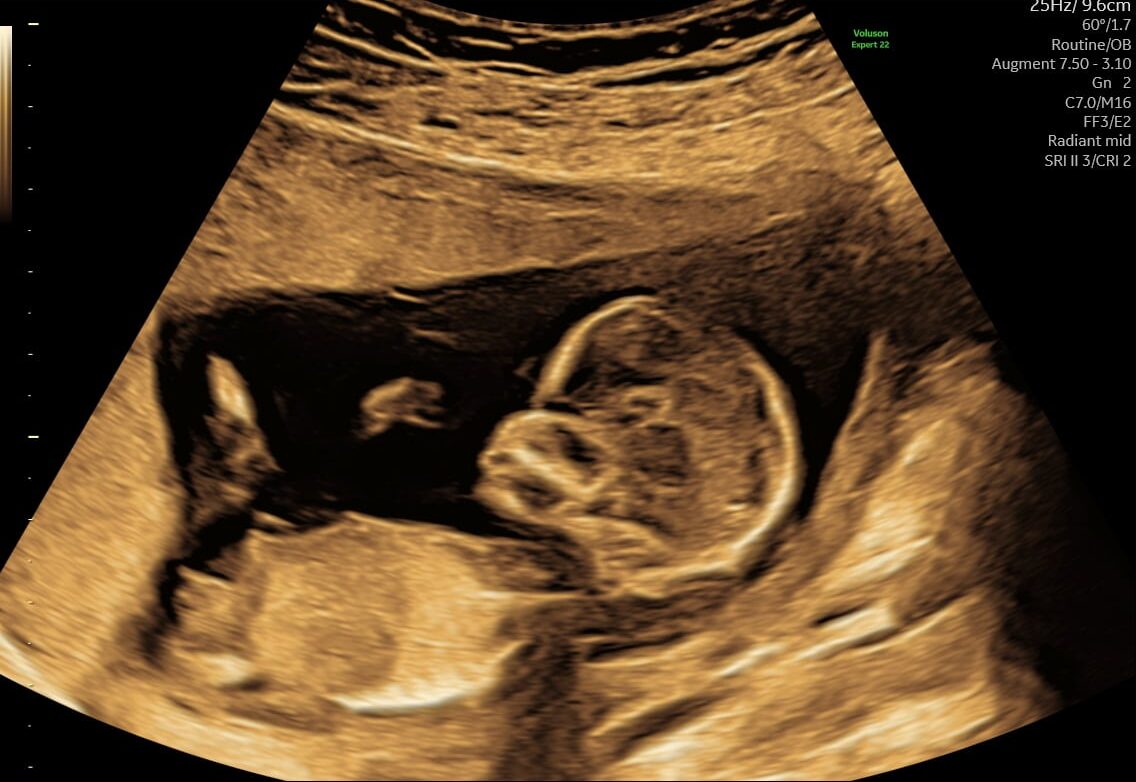

Mange kommende forældre glæder sig til at få at vide, om det er en lille dreng eller pige, der er på vej. Allerede fra uge 14+0 kan vi med en kønsscanning se barnets køn.

Hos os bliver du mødt af specialiserede jordemødre, der med stor erfaring og nyeste ultralydsteknologi giver dig en tryg og præcis scanning. Vi ved, at det kan være en særlig milepæl i graviditeten – både følelsesmæssigt og praktisk, når man gerne vil forberede sig på den lille ny.

En kønsscanning hos os handler derfor ikke kun om at få svaret på dreng eller pige, men også om at skabe en rolig og nærværende oplevelse for jer som familie.

Kønsscanning afslører dit barns køn fra uge 14+0 – og du kan supplere med en 3D/4D scanning for at få detaljerede billeder.

- Ved en kønsscanning hos praksisjordemoder får du en fin 2D kønsscanning af bedste kvalitet, hvor vi udover at se kønnet ser hjerteblink og lytter til det. Du kan se hvordan den lille ligger og bevæger sig, og det er tydeligt at se hvor hurtigt den lille udvikler sig i maven.

Udover at se kønnet er det bare så dejligt at få et lille ekstra kig ind til den lille på det her tidspunkt i graviditeten, de fleste mærker ikke liv endnu og der er stadig lidt tid til den næste scanning. Er du klar at vide om du skal have en lille dreng eller pige, så book en kønsscanning allerede i dag.